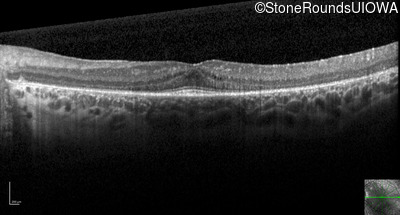

Optical Coherence Tomography - Left - 20/32 sc

Exemplar / OCT Stack

OCT Stack